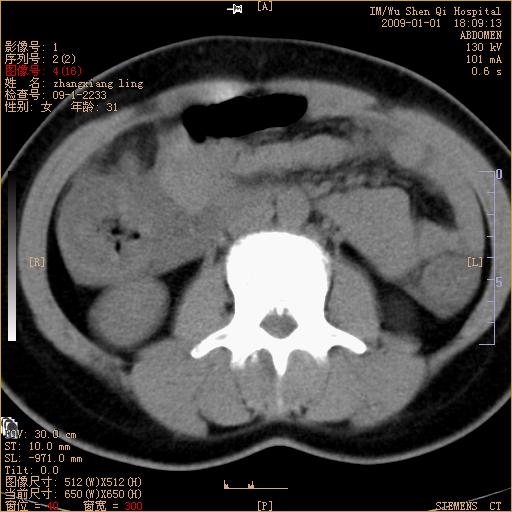

标题: CT17527:F31Y,腹痛伴血便9小时 [打印本页]

标题: CT17527:F31Y,腹痛伴血便9小时

升结肠肠壁不规则增厚,肠腔狭窄,考虑升结肠占位,建议增强扫描

升结肠肠壁不规则增厚,肠腔狭窄,考虑升结肠占位,建议增强扫描,不除外肠套叠.

升结肠肠壁不规则增厚,似呈同心圆改变,其有积液。结合病史首先考虑肠套叠伴肠壁坏死可能性大,结肠肿瘤待排。

升结肠肠壁不规则增厚,似呈同心圆改变,其有积液。结合病史首先考虑肠套叠伴肠壁坏死可能性大,结肠肿瘤待排。支持!(发病急,无过去史,应首先考虑:肠套叠)

患者已手术,结果肠系膜血栓形成肠坏死

患者已手术,结果肠系膜血栓形成肠坏死。

结合病史并看到升结肠增粗及局限的腹腔积液,考虑肠套叠伴肠壁坏死可能性大

结果:患者已手术,结果肠系膜血栓形成肠坏死。回过头再看局部肠壁增厚有分层(高密度坏死及低密度水肿)表现。